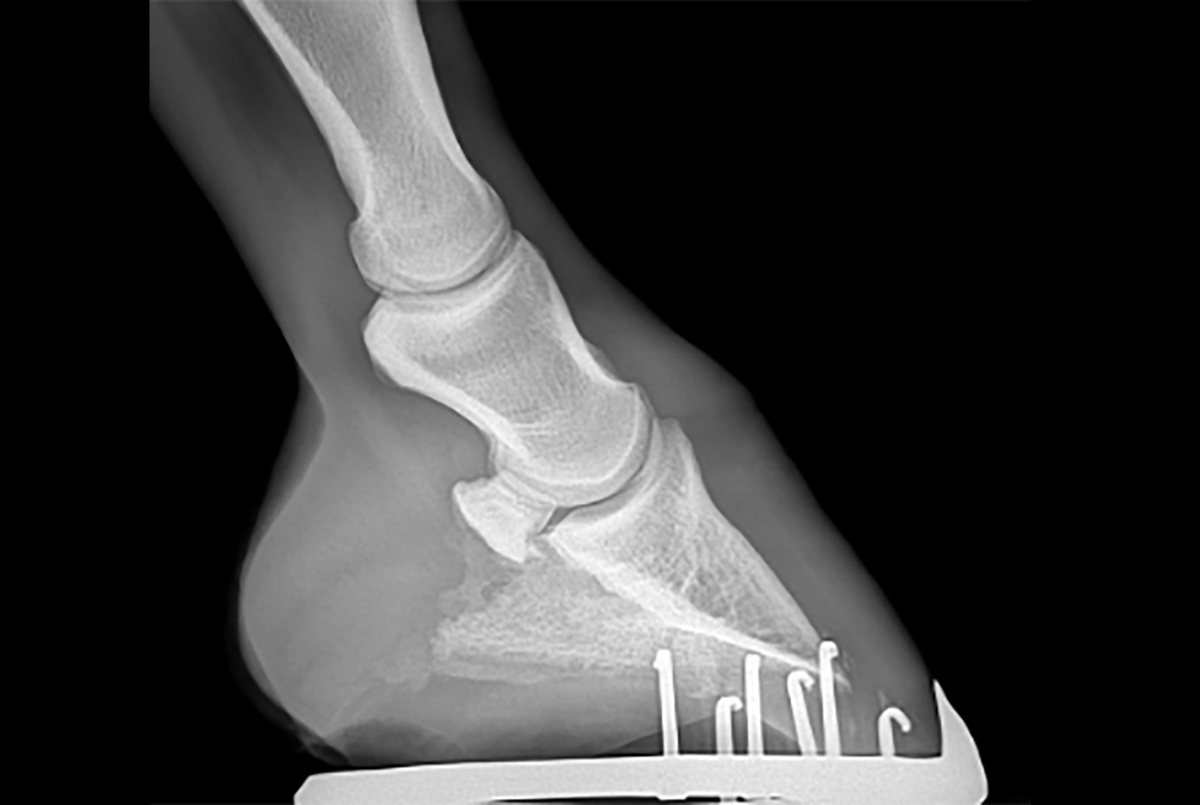

Rentgenový nález (cysty v kosti, rozšířené cévní kanálky, nárůstky na úponech vazů) nemusí vždy korespondovat s mírou bolesti. Existují koně s „ošklivými“ snímky, kteří nekulhají, a naopak koně s „čistým“ rentgenem, kteří trpí bolestí měkkých tkání (vazů a burzy), které rentgen neukáže.

- Rentgen: pro posouzení kostních změn.